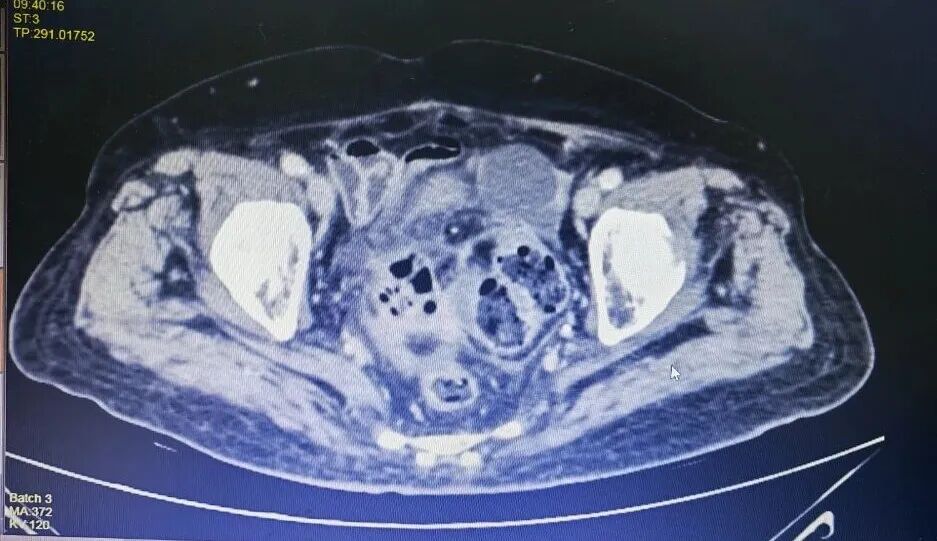

CT下病灶

尤其是结肠癌合并脓肿及不完全性梗阻,胆囊结石伴胆囊炎,随时可能引发感染加重、穿孔、脓毒症等危象;而患者同时存在的动脉硬化、髂动脉血栓,更如同“定时炸弹”,术中术后随时可能因血栓性疾病导致危及生命;加上肾功能不全、痛风等,使得麻醉和手术风险增加。